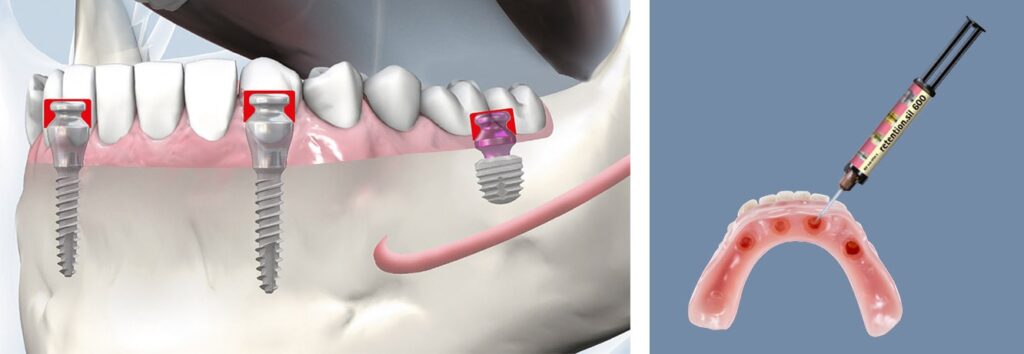

copaSKY TiSi.snap, sinir veya sinüs üzerindeki posteriorlarda sınırlı kemik yüksekliği olan restorasyonlarda, çıkarılabilir restorasyonları desteklemek için ideal bir çözümdür. Ön bölgede miniSKY ve TiSi.snap ile birlikte ideal. Protez üzerinde sabitleme: